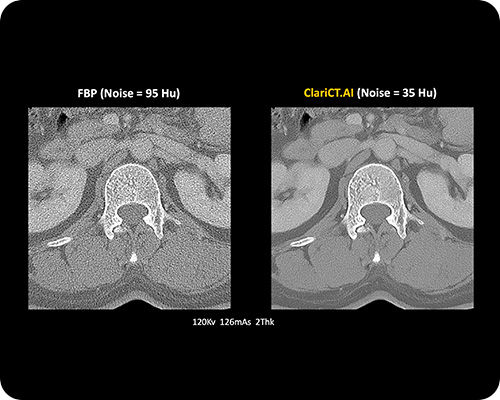

ClariCT.AI

AI-Powered Radiation Reduction

The first AI software that dramatically reduces radiation exposure while delivering the highest quality CT images using advanced AI denoising technology.

Reduces radiation exposure by 70-95% while maintaining superior image quality